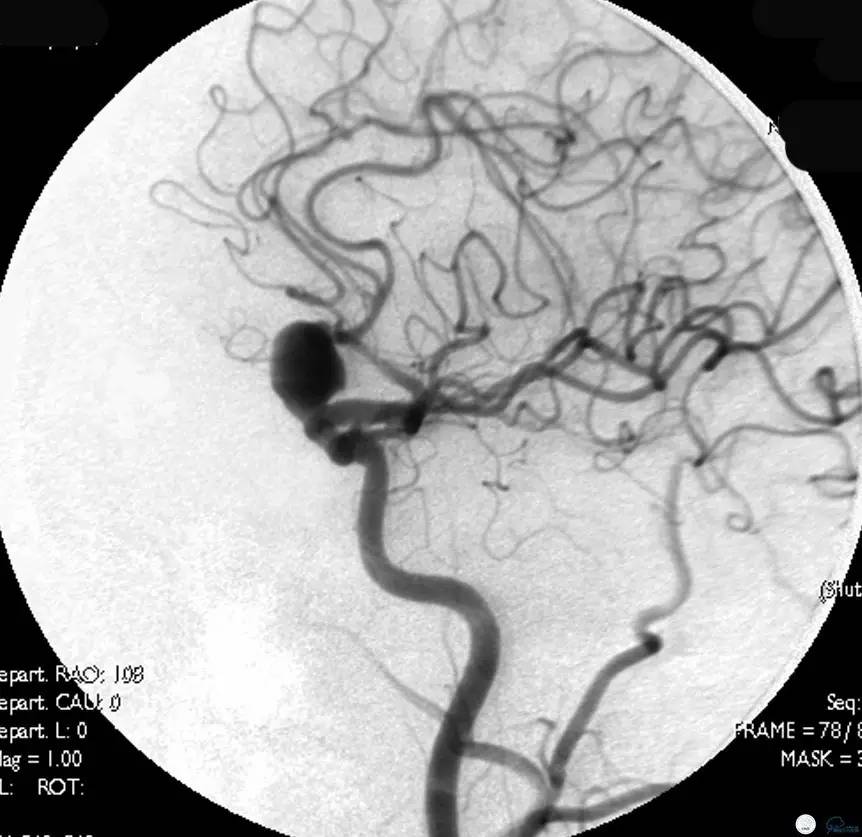

Case1 右ICA多发床突旁动脉瘤